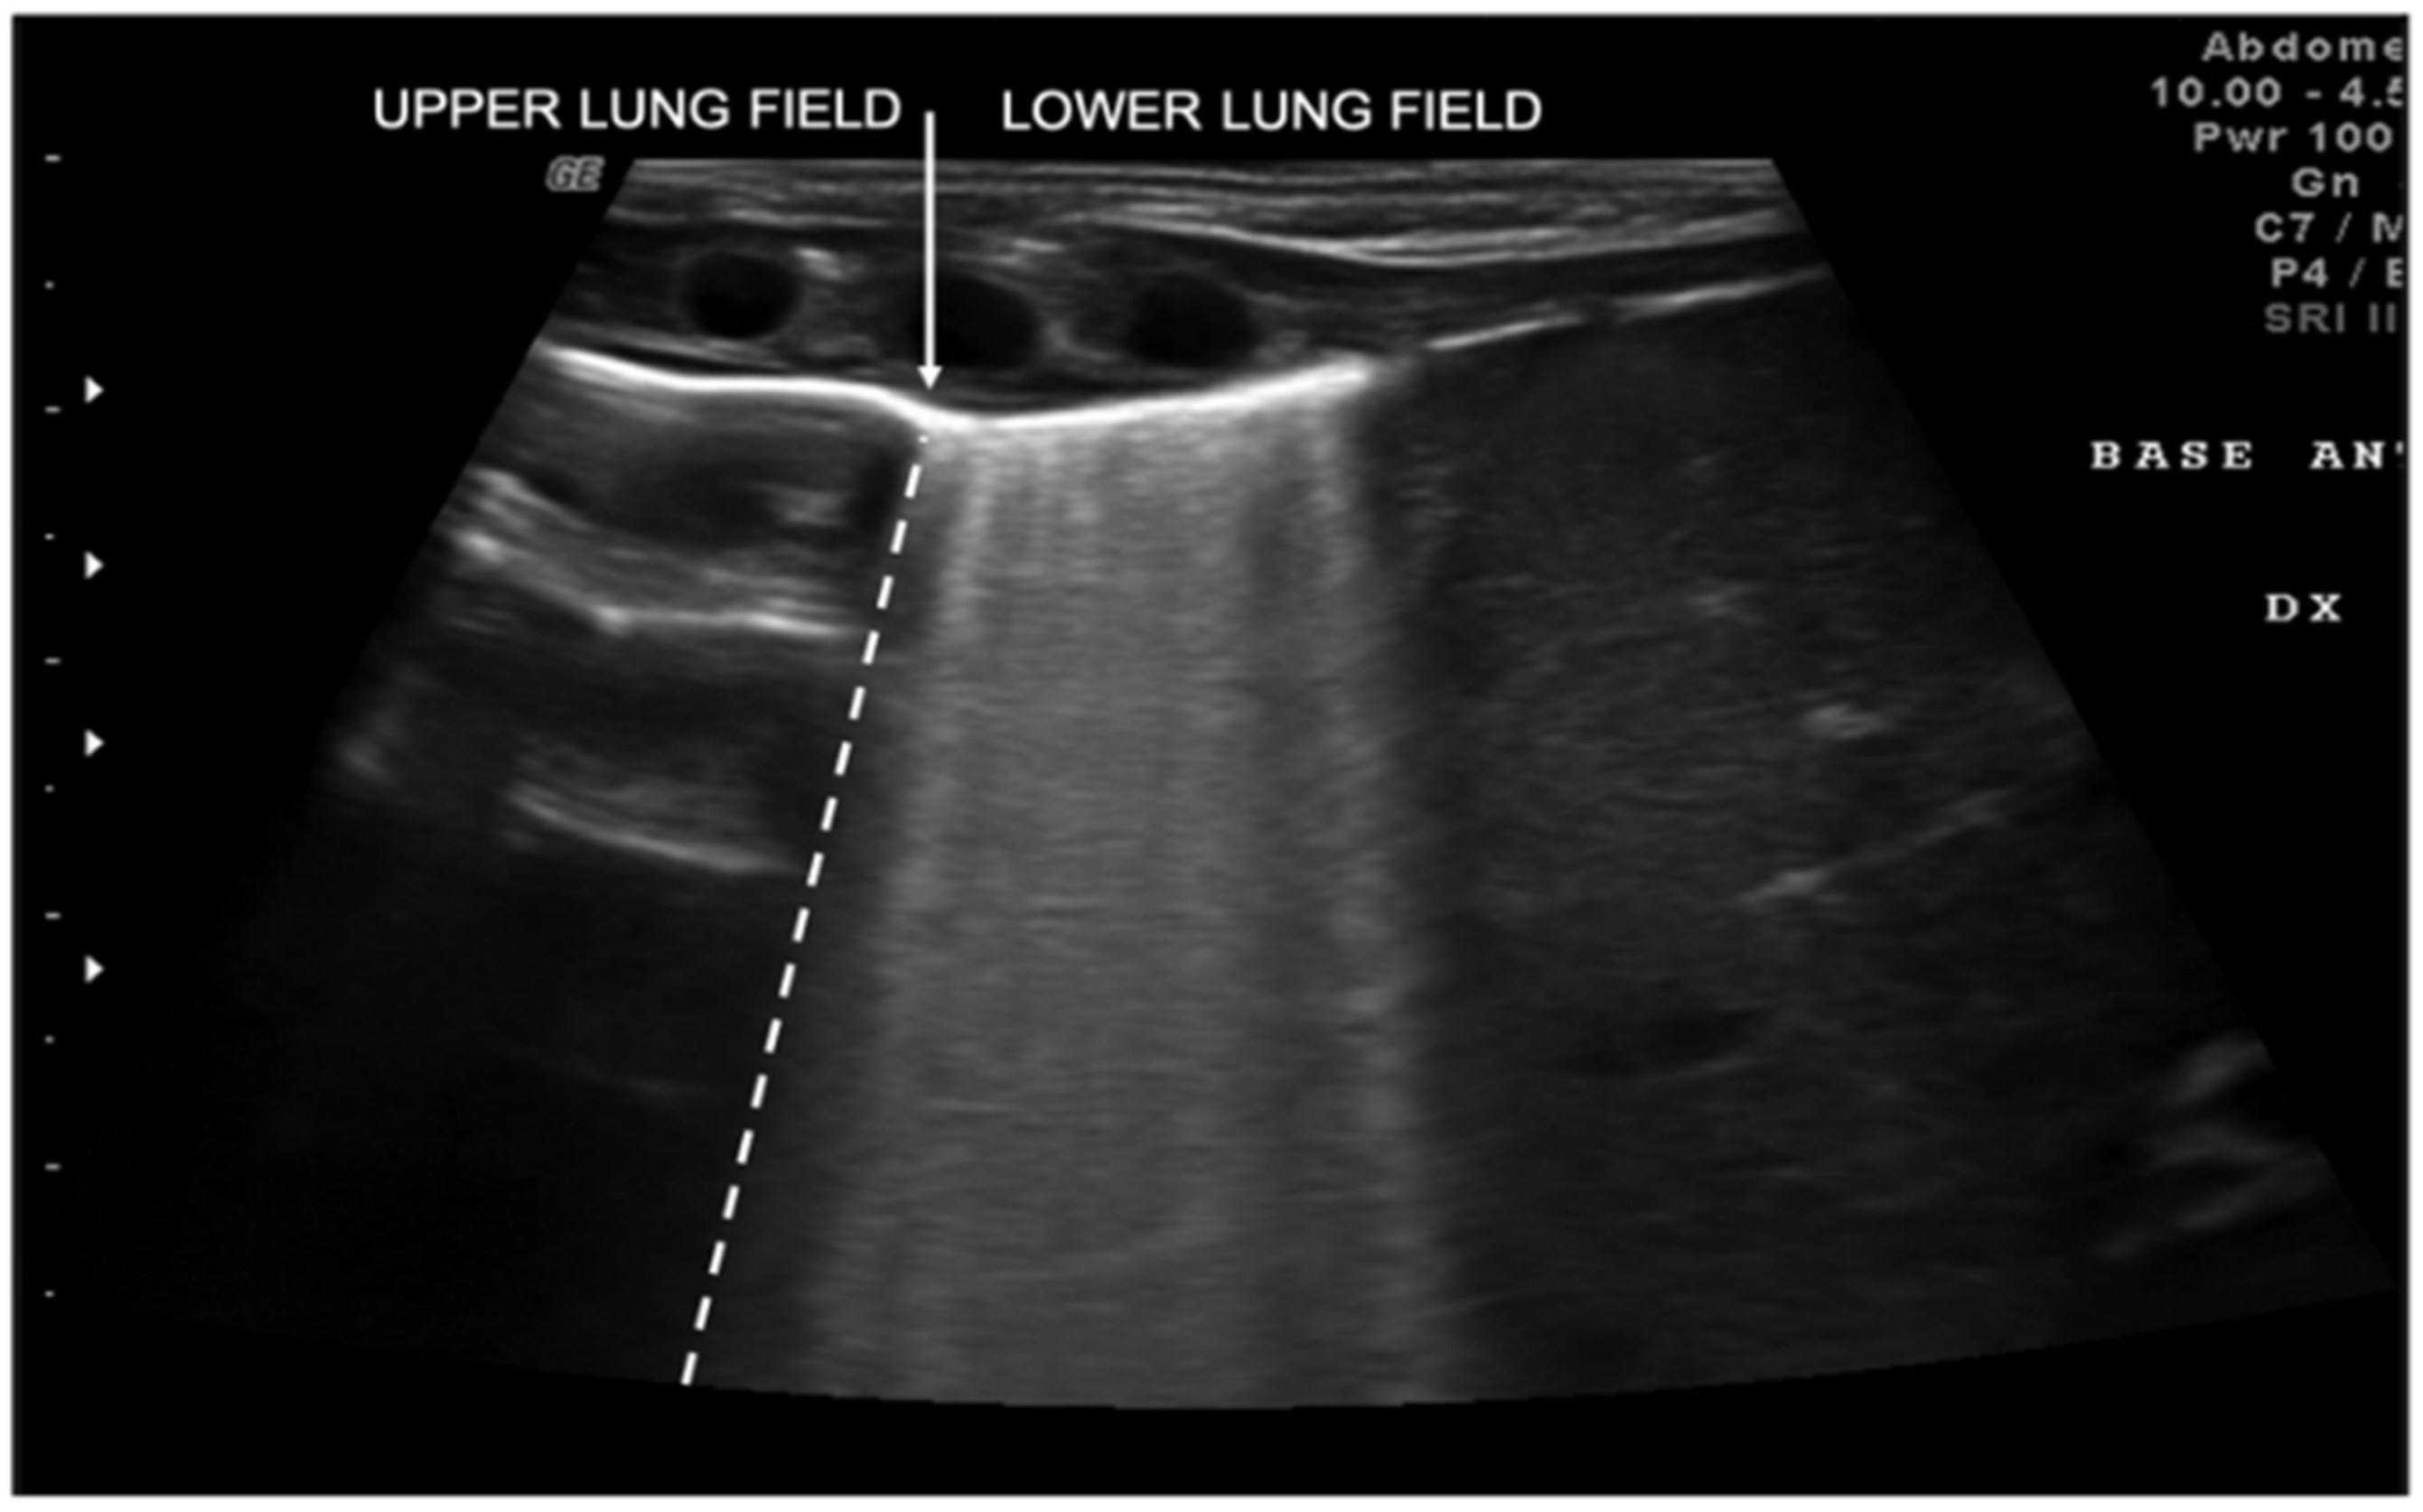

Transient tachypnea of the newborn (TTN), also known as “wet lung,” is caused by a failure in the reabsorption of fluid from the fetal lung. It is typical of term or post-term infants in the case of rapid delivery or cesarean section [24]. Infants with TTN present compact B-lines in the lower lung fields and fewer and less compact B-lines in the upper fields in one or both lungs. These signs, also known as double-lung points, appear because of the greater involvement of the lower lung fields in the disease and are characterized by a sharp ultrasound demarcation line between the upper and lower lung fields of both lungs (Figure 5) [17]. The pleural line is regular, with normal echogenicity and movement with respiratory acts. In contrast to NRDS, no subpleural consolidations are observed. Due to these typical ultrasonographic findings, much evidence has shown how pulmonary ultrasonography can be useful in the early diagnosis of TTN and differentiate TTN from NRDS already by the first hours of life [25].

Figure 5.

Transient tachypnea of the newborn. The dashed line shows the ultrasound demarcation line between the upper and lower lung fields: double-lung point (white arrow).